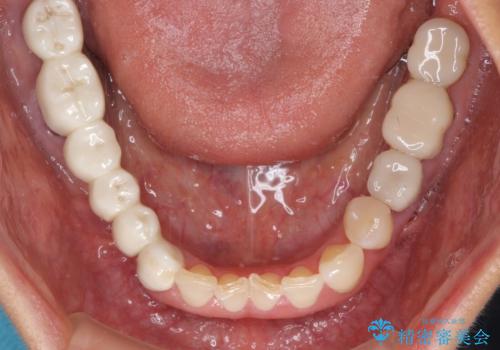

- 以前治療した歯が欠けたり、痛みを感じたりしているとのことで来院された患者様です。

アメリカ国内を転々としながら治療を行ったため治療跡がモザイク様で、クラウンが壊れていたり、抜歯が必要であったりしていました。

上下左右すべての奥歯に処置が必要であり、同時に行うと食事が取りにくくなってしまったり、手前の歯に負担がかかって初診時よりも状況が悪化したりする可能性があるため、片方ずつ処置を進めて行くこととしました。

下顎右側は骨造成を併用してインプラント治療を行い、その他の奥歯もインプラントや歯周外科処置を併用して補綴治療を進め、最後に前歯部の欠けてしまったセラミッククラウンを作り替えることとしました。